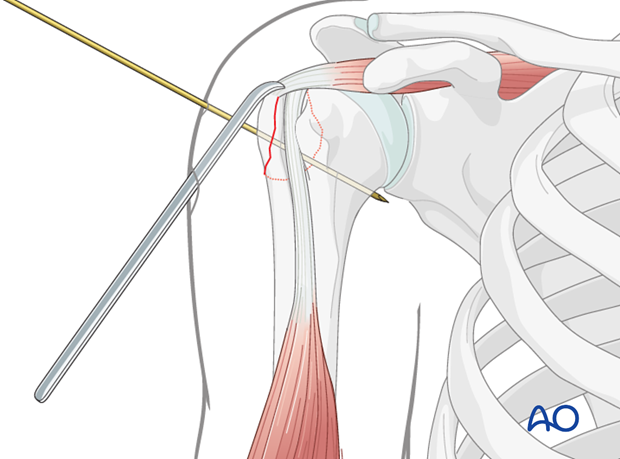

* Temporary K-wire fixation can be used to maintain reduction while definitive screw fixation is planned and applied.

This image demonstrates the temporary K-wire fixation maintaining the reduced greater tuberosity fragment, a common step before inserting definitive screws.

This image demonstrates the drilling of the pilot hole for screw insertion after reduction and temporary fixation.

This image shows the measurement of screw length after drilling, ensuring appropriate purchase without violating the articular surface.

- Drill Glide Hole: For the GT fragment, a drill bit matching the screw's outer diameter is used to drill a hole through the GT fragment. This is the "glide hole" which allows the screw to slide freely through the fragment.

- Drill Thread Hole: Using a smaller drill bit (matching the screw's core diameter), a pilot hole is drilled into the humeral head.

- Measure Depth: A depth gauge is used to determine the appropriate screw length.